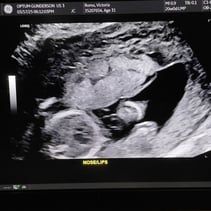

Greetings! I’ve been away from my updates for a couple of weeks, so lets get you caught up on all the things! First off, we had our Anatomy Scan today and hit the half way mark of the pregnancy. WOW. Our baby girl is doing so so well. From head to toe, she’s about 9-10inches and weighs 12oz. A week or two ago I stopped having all pregnancy symptoms besides the obvious physical changes. This was awesome but also made me a little uneasy. I also have not felt much movement and waiting 4 weeks for my 20 week appointment was starting to make me very antsy in a horribly, anxious way. Having a miscarriage the first time around has really made it difficult to relax and feel confident that everything is going well. Last week Steven went ahead and bought me a Doppler to listen to our baby’s heart beat at home while we waited for our next appointment. Once it came in and I found that wonderful sound of her heart, whew! Instant relief. Today was even better! Not only is SHE healthy, but so am I! I started going to the gym a few days out of the week and signed myself up for a 4 week Prenatal Yoga class that takes place every Saturday. My blood pressure today was 118/72 and weighing 129 which is 4 pounds more than my last appointment. I feel wonderful and even more excited than I was before to meet our girl! We’ve started clearing out the room that will be her nursery and are so grateful to the friends and family that have already started pouring their love into us and our baby with the registry gifts! Steven also surprised me with setting me up to visit family in Texas next month during my Spring Break from work. What a guy. 💕 I hope you all enjoy these photos! You‘ll see her profile with her cute little nose! There’s one of her foot, one of her crunched up with her legs bent, a crazy one of her that looks like a Halloween photo, and it’s hard to tell but one of her lips and nose. She was spinning and drinking and kissing us while she was having her first photoshoot. I will start feeling her more in the next couple of months. I have an anterior placenta so it makes things a little harder to feel since its placed in the front of my uterus. She is having fun, nonetheless. That’s all for now! We love you aaalllllll. A note from Steven: we could clearly tell during the sonogram that she gets her dance moves from her daddy.